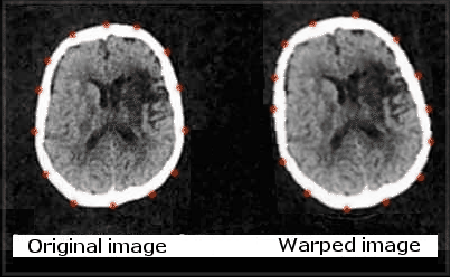

There are important factors to consider when selecting a transformation method. One such factor is the property called diffeomorphism. Diffeomorphic [] functions are invertible, continuous and one-to-one mappings, which can be applied to a given image. Diffeomorphic transformations that are used in this work were initially devised by Twining and Marsland [] (see the example in Figure [*]). These benefit from having continuous derivatives at the boundaries unlike, for example, those proposed by Lötjönen and Mäkelä [].

Figure: An example of image warping in medical contexts (the human brain). Points that are overlaid on the skull depict knot-points for the splines that render a transformation, which is based on clamped-plate splines. The image on the right is a warped and tilted version of the original on the left.